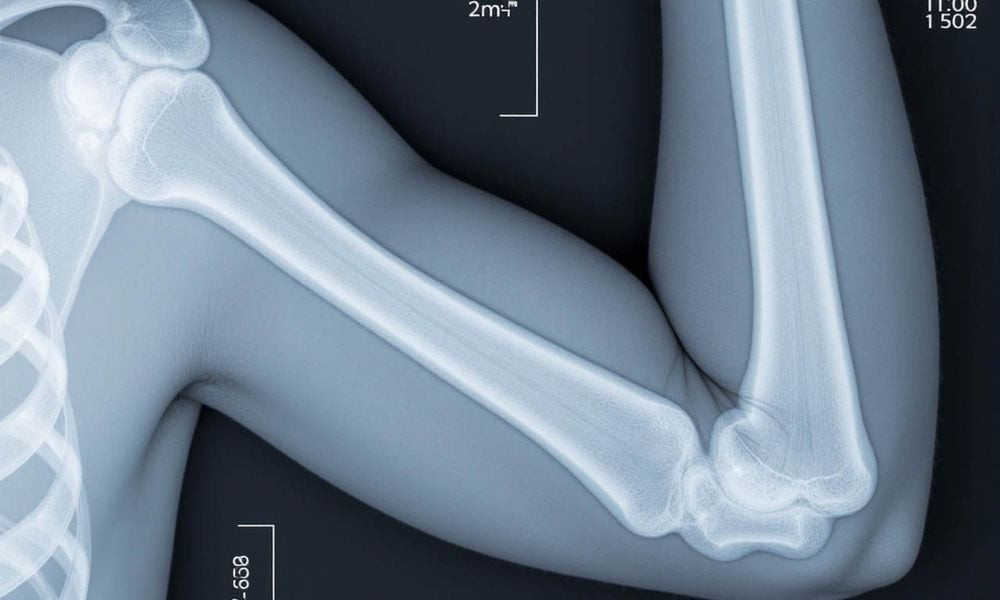

Phương pháp phổ biến và được khuyến nghị rộng rãi nhất để đo loãng xương hiện nay là DEXA scan (Dual-energy X-ray Absorptiometry). Kỹ thuật này sử dụng tia X năng lượng thấp để đo lượng canxi và các khoáng chất trong xương tại các vị trí quan trọng như gót chân, cột sống, hông, tay hoặc cổ tay. Mật độ xương cao thường đồng nghĩa với xương chắc khỏe và nguy cơ gãy xương thấp hơn.

Ngoài ra, việc đo mật độ xương (BMD) bằng DXA tại khớp háng hoặc cột sống thắt lưng còn giúp chẩn đoán loãng xương, đánh giá mức độ nghiêm trọng, dự báo nguy cơ gãy xương và theo dõi hiệu quả điều trị. Các phương pháp tầm soát khác như đo mật độ xương tại các khu vực ngoại vi (gót chân hoặc ngón tay) bằng DXA hoặc siêu âm cũng được sử dụng để sàng lọc trong cộng đồng.